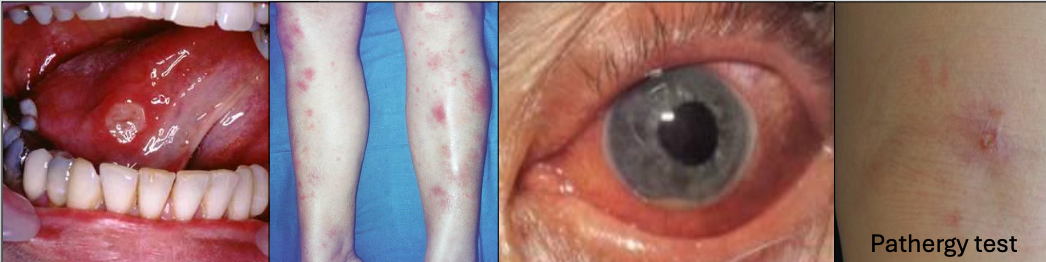

What is Behçet Syndrome?

A chronic recurrent autoimmune disease,20’s and 30’s, Mediterranean or Asian descent (Silk road)

What is the criteria for diagnosis of Behçet Syndrome?

Recurrent oral ulcers 3x/yr + 2 of

Recurrent genital ulcerations (75%)

Eye lesions (70%)

Skin lesions

+ pathergy test (results are variable)

In which condition do you see arthritis

Behçet Syndrome